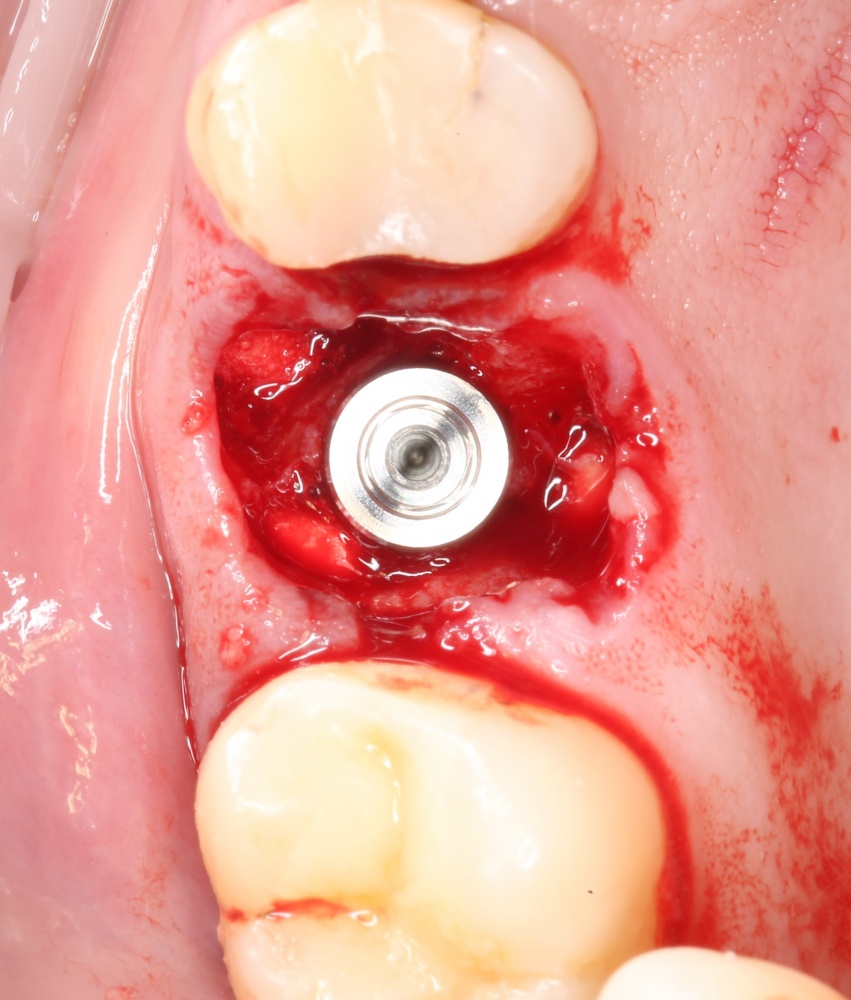

Каковы показания к открытому синуслифтингу? Когда его можно проводить совместно с установкой имплантов. а когда лучше сделать отдельным этапом?

Как правильно и аккуратно сделать доступ в верхнечелюстную полость? И как создать достаточное по объёму субантральное пространство?

Как реабилитировать пациента после операции синуслифтинга и как минимизировать риск возможных осложнений?